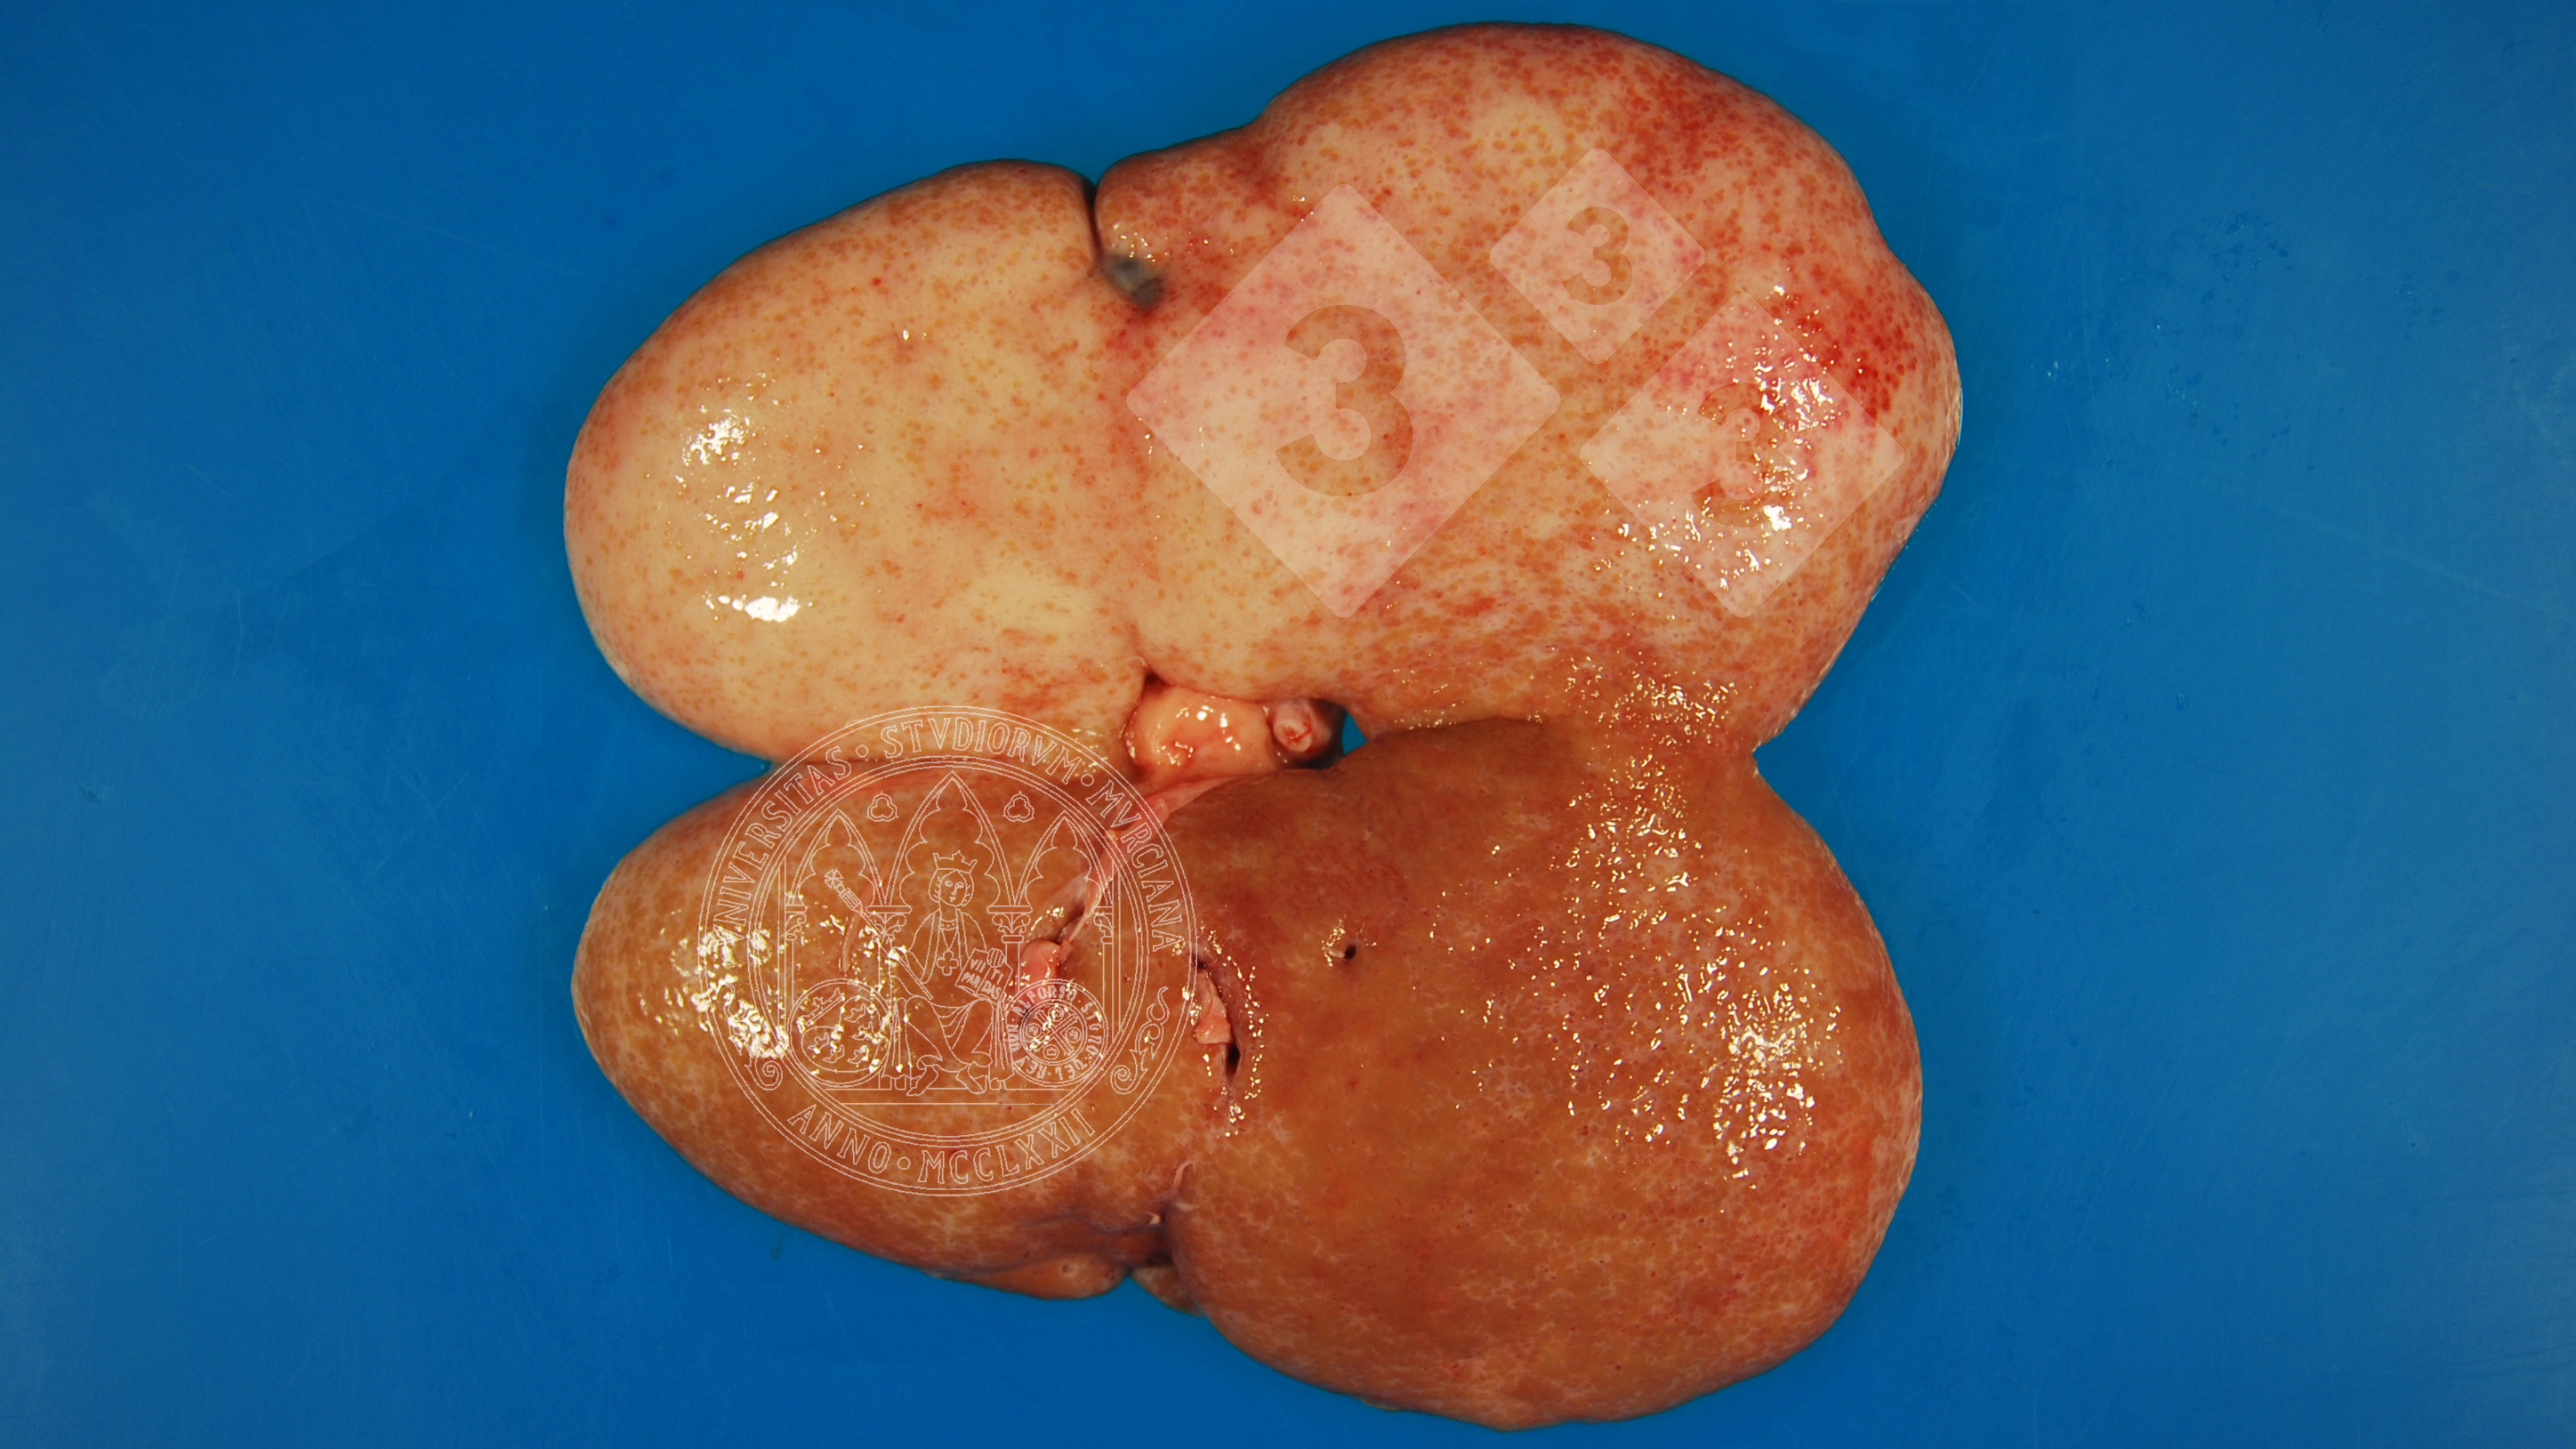

The open kidney of a fattening pig appears whitish on most of the surface with irregular contours. This is a chronic process of fibrosis (sclerosis) as interstitial nephritis progresses, and is clinically associated with chronic renal failure.

A differentiation must be made between this lesion and other chronic or degenerative inflammatory processes.